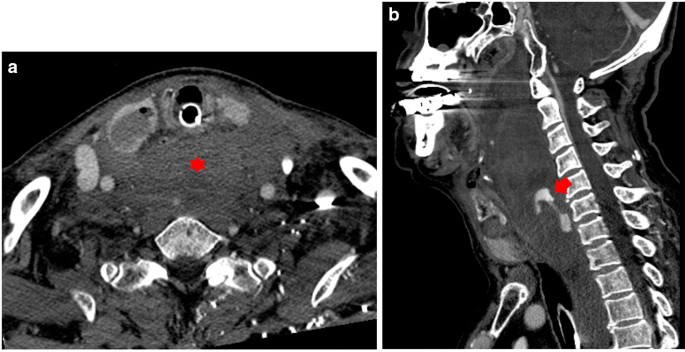

An 80 year-old man underwent ultrasound-guided FNA of the thyroid gland with a 23-gauge needle for the evaluation of a 1.8 × 2.2 cm well-defined, cystic nodule with internal tiny solid portion in the right lobe, which was identified by contrast-enhanced chest computed tomography (CT) taken one month before FNA (Fig. 1). Two passes were made into the lesion during the procedure. There were no complications during the procedure. Three hours later, the patient experienced swelling and progressive pain in the anterior neck. He was referred to the emergency room of our hospital with severe respiratory distress, four hours after the FNA. Emergency intubation was performed, and the patient remained hemodynamically stable. The patient was on a long-term anticoagulant medication prescribed for cardiovascular disease. Although the platelet count and liver functions were within normal range, the International Normalized Ratio (INR) was 1.35 (normal range: 0.085–1.15). An axial neck CT taken on emergency department revealed a large hematoma in the retropharyngeal space that caused anterior tracheal deviation (Fig. 2a). The sagittal neck CT showed extravasation of contrast media, suggesting active bleeding within the hematoma (Fig. 2b). Angiography was performed as a primary diagnostic and therapeutic procedure. Right subclavian angiography showed active bleeding arising from the right thyrocervical trunk in the neck, corresponding to the CT image (Fig. 3a). The right thyrocervical trunk was selected, and the culprit vessel was identified as the branch of the right inferior thyroid artery (ITA) (Fig. 3b). After superselection of the right ITA using microcatheter, embolization of the right ITA was performed using NBCA, and a post-embolization angiogram revealed successful hemostasis without active bleeding (Fig. 4). Although the retropharyngeal hematoma still remained, the patient’s respiratory rate was very stable under intubation state, and there was no evidence of increase in hematoma, which was confirmed on a daily follow up neck x-ray. Considering the risk of procedure-related complications, we decided to maintain conservative management for the hematoma. Six days after the embolization, when the patient was able to breathe around the endotracheal tube, it was removed without accident. Follow-up CT taken three weeks after TAE revealed a low-density lesion in the retropharyngeal space, indicating an old hematoma, which was smaller than it was before TAE without further treatment such as percutaneous drainage or open excision (Fig. 5). The patient recovered well and was discharged four weeks later. The hematoma in the retropharyngeal space was completely eliminated, which was confirmed by follow-up CT taken three month after the TAE, performed in an outpatient clinic. Unfortunately, we failed to obtain enough blood sample through the FNA, so failed to obtain the final pathological report. Additional FNA was not performed because the patient refused to take further work up for the thyroid nodule.

a An axial neck CT take after thyroid FNA underwent on emergency department reveals a large hematoma (red asterisk) in the anterior neck space with anterior tracheal deviation and nodule in the right thyroid lobe with intra- and extra nodule air-bubbles caused by the fine needle aspiration. b Sagittal CT scan shows extravasation of contrast media suggesting active bleeding (red arrow) within the hematoma